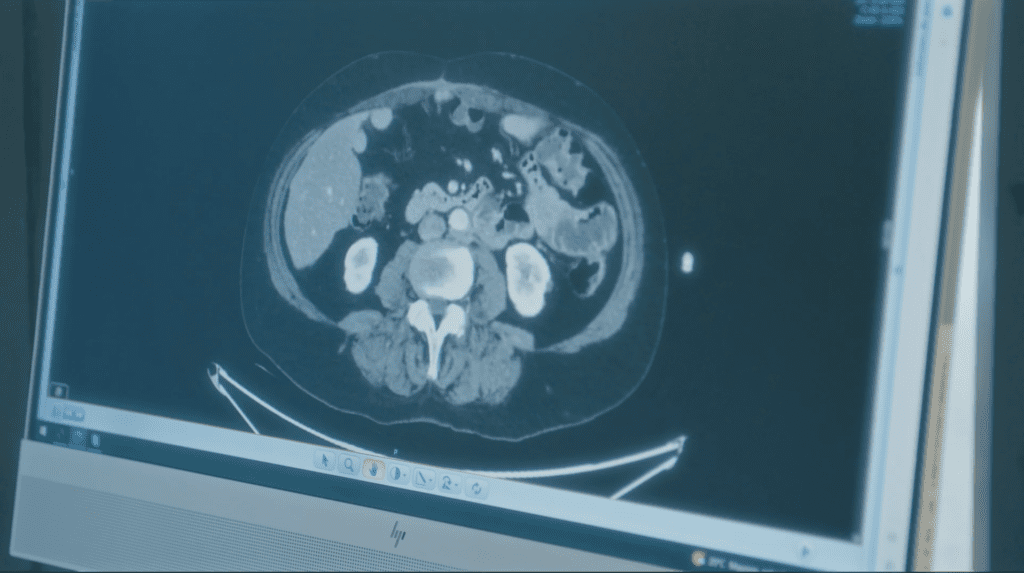

• Tomografía computarizada (TAC)

TAC es una técnica de obtención de imágenes anatómicas mediante rayos X y procesamiento computarizado. El TAC puede detectar lesiones metastásicas con un diámetro superior a 1 cm. Para identificar metástasis más pequeñas, a menudo se requiere una laparoscopia diagnóstica.

El Índice de Carcinomatosis Peritoneal (PCI) se utiliza para describir el volumen del tumor presente en la cavidad abdominal. La tomografía computarizada (TAC), la resonancia magnética (RM) y/o la laparoscopia diagnóstica se pueden utilizar para evaluar el PCI antes de la cirugía, pero la determinación final se realiza durante el procedimiento de CRS + HIPEC. La valoracion intraoperatoria del PCI, así como la puntuación de CC (cumplimentacion de la cirugía), son fundamentales para determinar el pronóstico después de la cirugía.